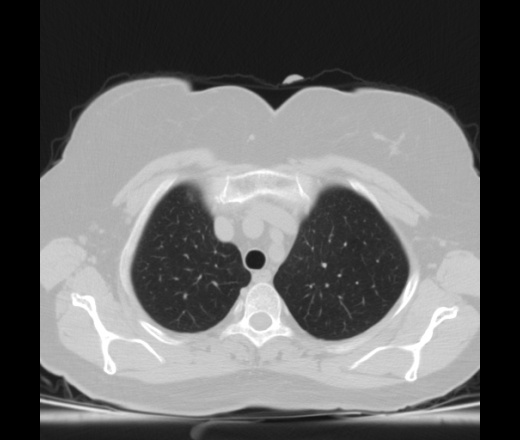

Женщина средних лет. Выраженные кардиалгические боли за грудиной, ранее не беспокоили, ни с чем не связывает, была доставлена в ОКЦ с подозрением на ОКС. Обследована, данных за ОКС нет. Перенаправили к нам с грудным остеохондрозом. Вариантов не было, госпитализировали. Невропатологи машут рукама, мол с какаих пор корешковый синдром с грудины начинается, не наша она. Консилиумом решено сделать КТ, зачем, сами не знают. ЭКГ б/о, кровь б/о. На ЭхоКГ у нас нашли какую то структуру в перикарде в области левого желудочка то ли жидкость, то ли жир, то ли сдавление из вне (по УЗИ я не разбираюсь, это со слов кардиолога который проводил исследование). Меня смущают только элементы жидкостной плотности обозначенные стрелками, их плотность от 0 до +7 Ед.Н.

И еще вот здесь жидкость.

Ну и жидкость и что? Если и есть медиастинит или перикардит он болеть не будет. Расширена левая легочная артерия. Тромбоэмболия? Я бы сделал с контрастом. При кардиологических исследованиях можно подключать ЭКГ-слежение и делать на кардиопрограмме. Тогда картинка будет лучше.